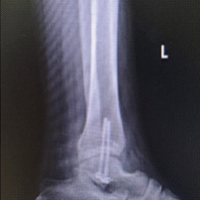

The perioperative period was uneventful, and the patient was started on partial weight-bearing walking with the aid of a walker after assessment of the reduction on the post-operative radiograph. He underwent suture removal on day 14 post-operative, and he had an uneventful recovery at the 6-week follow-up. However, he presented 2 weeks later with pain in the proximal thigh and a palpable hard mass. The patient did not report any history of accidental falls, was afebrile, and the local site was unremarkable. The inflammatory indicators were within the normal range (erythrocyte sedimentation rate 18 mm/h, C-reactive protein 2 mg/dL). Our clinical diagnosis was screw pull-out, varus collapse, and implant failure; however, imaging revealed that the distal half of the helical blade had uncoupled from the blade and was impinging on the skin (Fig. 4 and 5).

Figure 4: Anterior posterior (a) and lateral radiograph (b) showing uncoupling of helical blade.

Following the diagnosis, we planned to remove the uncoupled component and wait for union. The uncoupled component was removed in the minor theatre on an outpatient basis (Fig. 6).

Figure 6: (a) Intact helical blade, (b) uncoupled component.